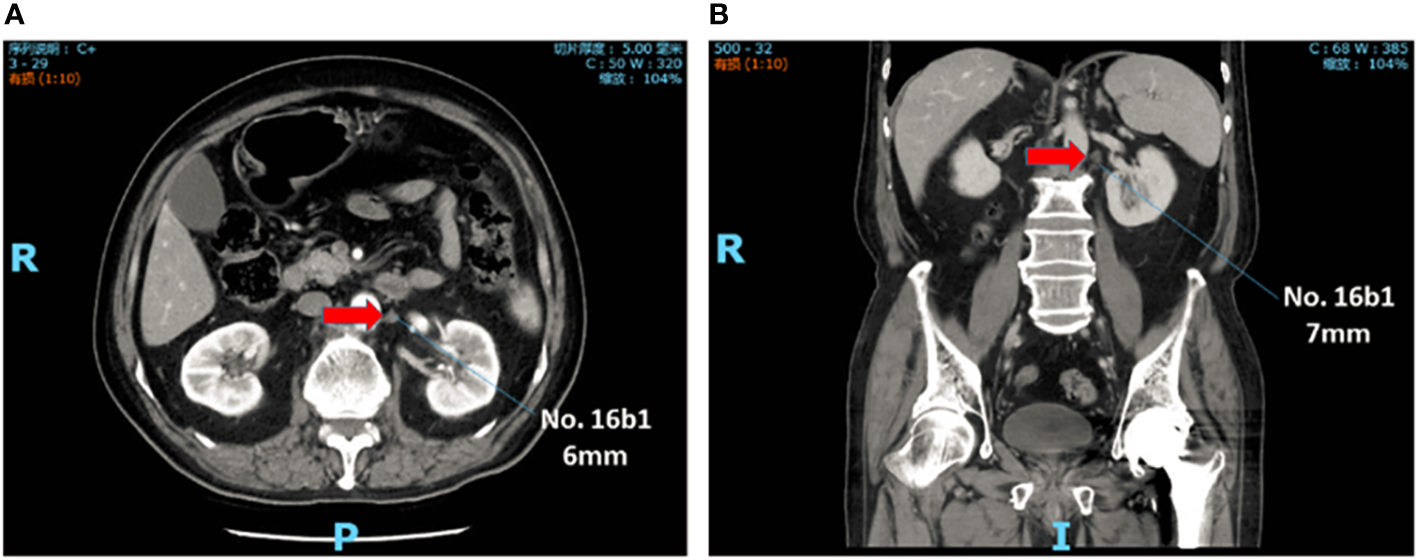

Abdominal contrast-enhanced CT scan was performed within 1 month before treatment. Skilled radiologists reviewed the images to evaluate cTNM stage. Furthermore, two experienced radiologists independently reviewed para-aortic region and reported the status and features of the PAN when it was detected. The results were presented in the form of location and size. The diameter of PAN less than 10mm was denoted as sPAN (Figure 1).

Figure 1

sPAN in abdominal contrast-enhanced computed tomography scan. The lymph node, with diameter less than lcm, was detected at No. 16b1. (A) Transverse plane. (B) Reconstructed image in coronal plane. sPAN, small para-aortic lymph node.